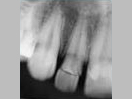

X-ray

Pre-Operation

After 3 months

x-ray post operation

After 2 years